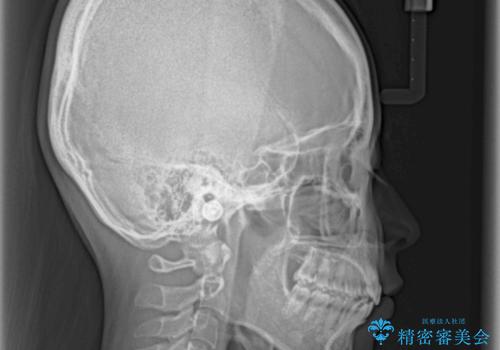

- 口元のデコボコと深い咬み合わせ(ディープバイト)を気にして来院された患者様です。

インビザラインによる上下歯列の拡大と、IPR(歯と歯の間を削る)にるスペースの獲得により、口元のデコボコとディープバイトを改善することとしました。